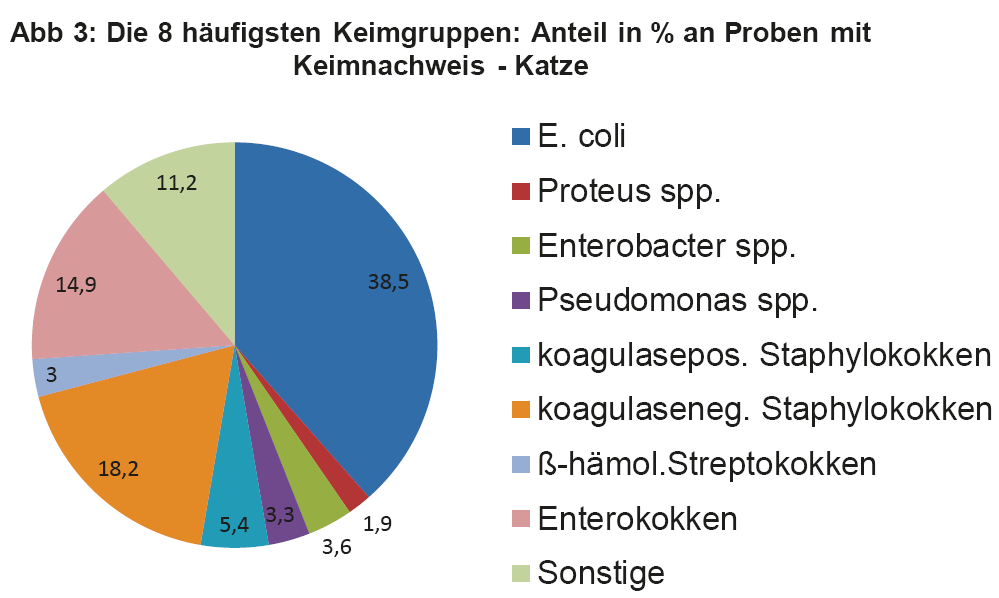

- Abb. 3: Die 8 häufigsten Keimgruppen: Anteil in % an Proben mit Keimnachweis – Katze

Wie bereits erwähnt, müssen die Therapieempfehlungen aus den ISCAID Richtlinien an unsere lokalen Verhältnisse angepasst werden. Daher ist es wichtig, sich regelmäßig über die aktuellen Keimnachweisraten und Resistenzmuster bei HWI zu informieren. Dies sollte allgemein, aber auch bezogen auf die eigene Praxis/Klinik, erfolgen. Regelmäßig durchgeführte BU bei HWI versorgen den Praktiker mit den wichtigen Zahlen. Man soll z.B. für die Ersttherapie keinen Wirkstoff auswählen, gegen welchen mehr als 10% der eigenen Patienten Resistenzen aufweisen. Da immer noch häufig Spontanurinproben statt Zystozenteseharn für die BU eingesandt wird, ist es wichtig, dass eine quantitative Auswertung der BU erfolgt, um Kontamination von Infektion abzugrenzen. Das Labor sollte die Antibiogramme nach den Standards von CLSI/EUCAST durchführen, wie es bei LABOKLIN der Fall ist (s. LABOKLIN aktuell 1/2015). In Abb. 2 und 3 sehen Sie die häufigsten Keimnachweise bei Hund und Katze aus dem Jahr 2013.

Die vier wichtigsten Keime bei der Katze sind E. coli, Staphylokokken (koagulasepositive und -negative) und Enterokokken. Diese machen zusammen sogar 77% der Nachweise aus. Um nun zu überprüfen, ob die in den ISCAID Richtlinien vorgeschlagenen Wirkstoffe für eine empirisch ausgesuchte Ersttherapie auch für unsere Verhältnisse Gültigkeit haben, muss man die Resistenzmuster dieser Keime einzeln überprüfen. Die Darstellung dieser Daten würde den Umfang eines LABOKLIN aktuell sprengen. Daher geben wir hier exemplarisch die wichtigsten Keime wieder. Abb. 4 zeigt die Resistenzverteilung von E. coli bei HWI vom Hund, die Verhältnisse bei der Katze sind ähnlich.